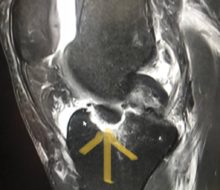

Por @pmpalermo Las holandesas maravillaron a todos en la semana mundialista de Innsbruck. Tras copar el podio de la contrarreloj individual, Anna Van der Breggen protagonizó un auténtico recital en la prueba en línea. Eminence fracture. Can’t believe it. So many emotions now. Will heal, but will take time… (weeks). pic.twitter.com/DFhzDeKw9Y — Annemiek van Vleuten (@AvVleuten) … Sigue leyendo Van Vleuten, 7° en el Mundial pese a estar fracturada